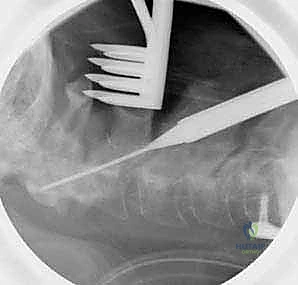

الخطوة 7: التصوير الشعاعي داخل العمليات

طوال الإجراء، وخاصة بعد تركيب المسامير والقضبان، يتم استخدام جهاز الأشعة السينية المحمول (C-arm